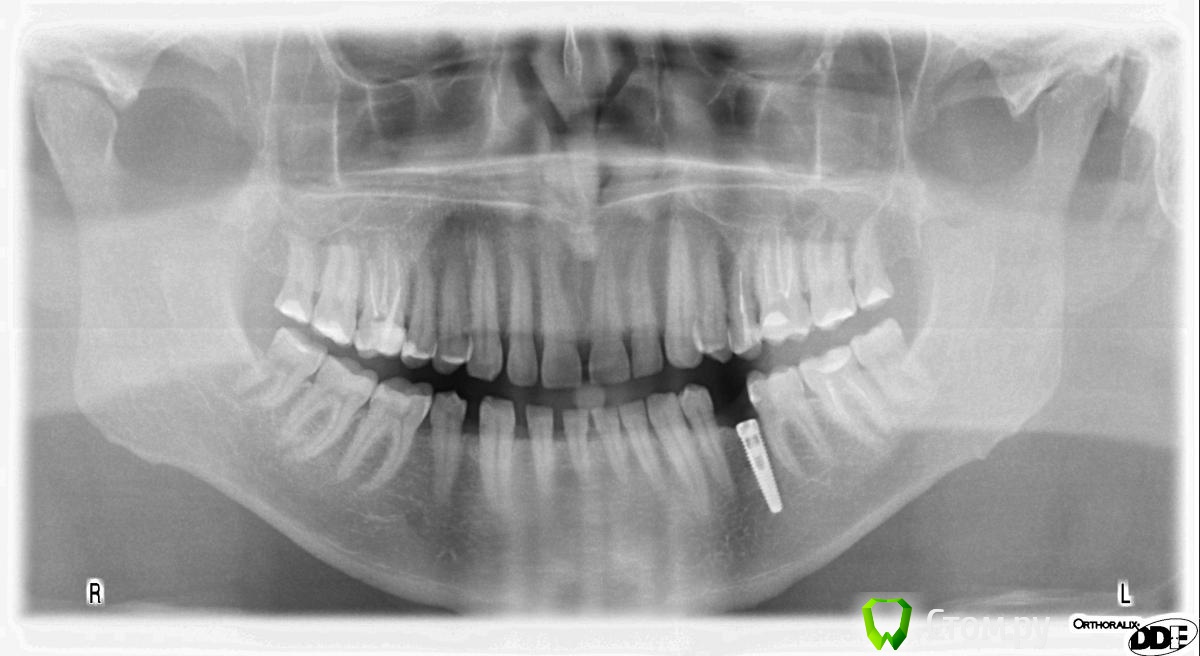

Rusty Опубликовано 23 сентября, 2014 Поделиться Опубликовано 23 сентября, 2014 Доброго дня. Подскажите, что за винты. Первый устанавливался около 7 лет назад в Москве. На следующем снимке импланты устанавливались в начале 90-х в Москве. Ссылка на комментарий

Дмитрий Никитюк Опубликовано 23 сентября, 2014 Поделиться Опубликовано 23 сентября, 2014 Нобель и 2 Ксайва. 3 Ссылка на комментарий

Rusty Опубликовано 23 сентября, 2014 Автор Поделиться Опубликовано 23 сентября, 2014 Нобель и 2 Ксайва.Сомнения по ксайву, может анкилос? Ссылка на комментарий

Дмитрий Никитюк Опубликовано 23 сентября, 2014 Поделиться Опубликовано 23 сентября, 2014 Сомнения по ксайву, может анкилос? Я в себе не сомневаюсь))). Анкилоз настолько специфичный имплантат, что спутать его с Ксайвом очень сложно. 7 Ссылка на комментарий

SDC Опубликовано 23 сентября, 2014 Поделиться Опубликовано 23 сентября, 2014 (изменено) Нобель и 2 Ксайва.Xive 3.4 справа и 3.8 слеваИ условий для протезирования нет...и на нобеле тоже Изменено 23 сентября, 2014 пользователем SDC 1 Ссылка на комментарий